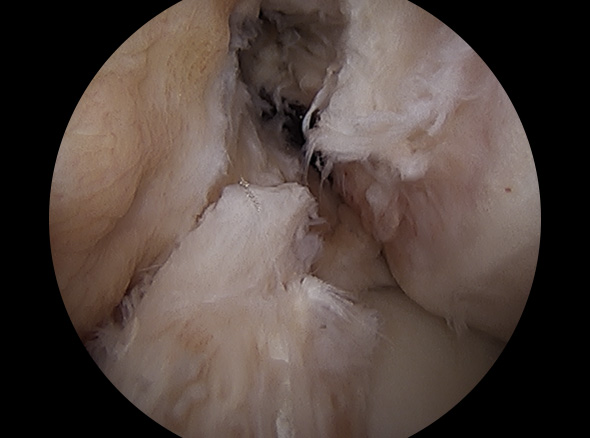

경골과 대퇴골 사이에 남아 있는 전방십자인대 제거

경골과 대퇴골 사이에